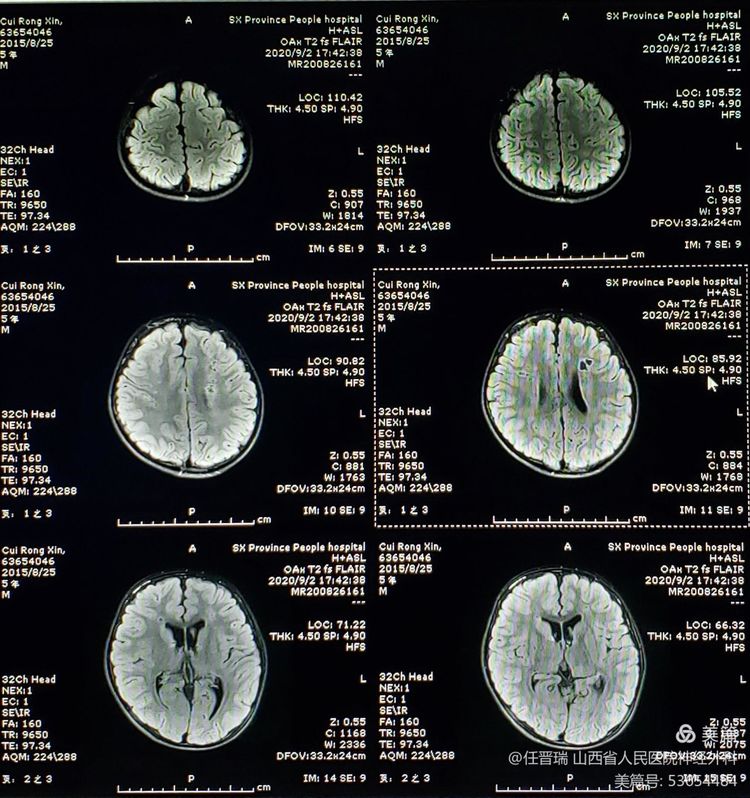

入院3月前颅脑MR: 双侧额顶叶可见多发急性脑梗死灶

入院前CT:经治疗脑梗死好转,左侧额叶脑内软化灶形成

术前MR:未见新发脑梗死